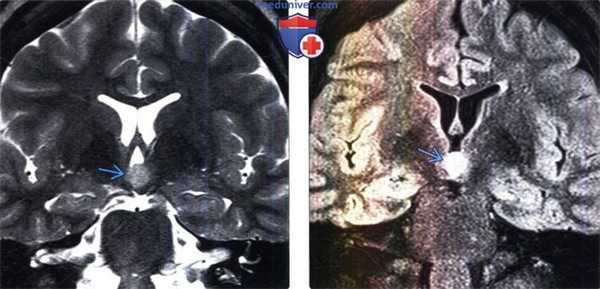

(Слева) МРТ, Т2-ВИ, корональный срез: у новорожденного с расщелиной основания черепа по срединной линии выявляются две воронки гипофиза, имеющие нормальные размеры и проходящие от зрительного перекреста к гипофизам.

(Справа) МРТ, Т1 -ВИ, корональный срез: визуализируются два гипофиза нормальных размеров, смещенные латерально и расположенные в основании черепа аномального строения. Гипофизы имеют однородный гиперинтенсивный сигнал вследствие влияния гормонов матери. В норме у новорожденных на Т1-ВИ гипофиз имеет диффузно гиперинтенсивный сигнал.

(Слева) МРТ, Т1 -ВИ, сагиттальный срез: у женщины 36 лет, обследованной по поводу судорожного синдрома, визуализируется супраселлярное объемное образование с четкими контурами, расположенное в пределах III желудочка.

(Справа) Тонкосрезовое корональное IR изображение: определяется объемное образование, расположенное в гипоталамусе. Это образование изоинтенсивно по отношению к серому веществу.

(Слева) МРТ, Т2-ВИ, корональный срез: у этой же пациентки объемное образование остается изоинтенсивным по отношению к серому веществу и на данной последовательности; оно приподнимает III желудочек, но не вызывает его обструкцию.

(Справа) МРТ, FLAIR, корональный срез: у этой же пациентки визуализируется образование, имеющее слегка повышенную интенсивность сигнала по отношению к коре. После введения контрастного вещества объемное образование его не накапливало. Это классическая гамартома гипоталамуса (ГГ) на широком основании.